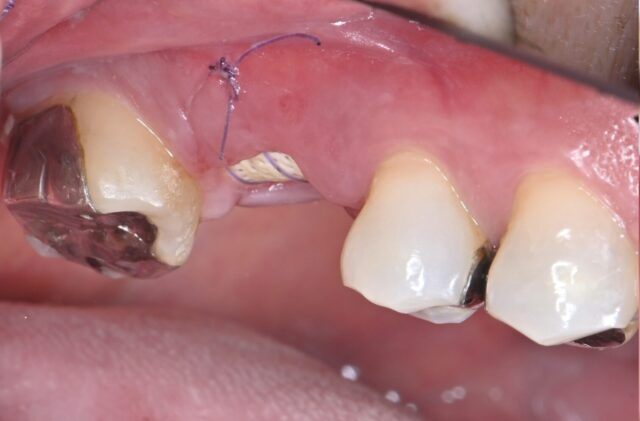

レーザーを使用して歯肉を大きく切開することなく第二大臼歯の歯石を取り除き、レーザーで溶けた骨の回復を促しました。抜歯の必要な第一大臼歯は、割れた線に沿って周囲の骨が溶けており、単純な抜歯を行うとインプラントを入れる骨がうしなわれる状態でした。抜歯後に歯を抜いた穴には骨の材料を入れ、メンブレンでフタをすることで、吸収を抑えるリッジプリザベーションという処置を行いました。

骨補填材を抜歯した穴へ入れています。これにより骨がしぼむことを防ぎます。

術直後。難度は高かったですが、メスを使うことなく手術を終了。

術後1日後。低侵襲な手術なため、1日で歯肉が落ち着き、膿の出ていた穴も、すでに肉眼では塞がっています。